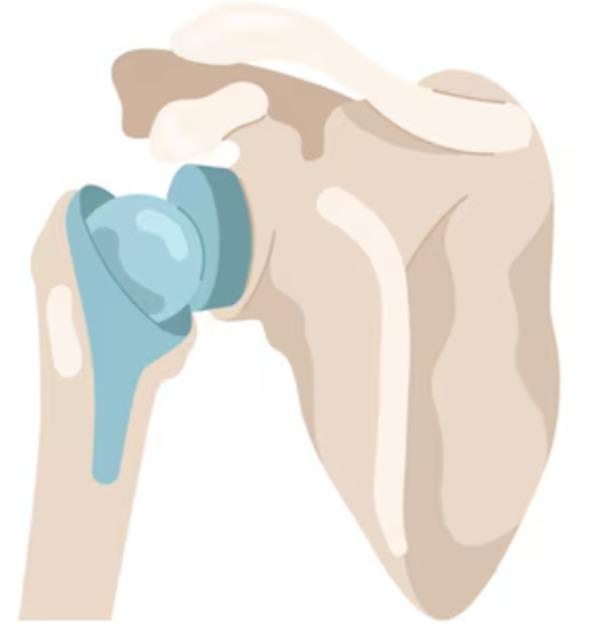

Shoulder Arthroplasty

Shoulder arthroplasty is a surgical procedure used to replace damaged or arthritic parts of the shoulder joint with artificial components. It is typically recommended for patients with severe osteoarthritis, complex fractures, or rotator cuff-related joint degeneration that limits mobility and causes chronic pain. At Rapha Sports and Regenerative Orthopaedics, our surgeons offer advanced shoulder replacement options tailored to each patient’s condition, lifestyle, and functional goals. Types of Shoulder Arthroplasty: Total Shoulder Replacement (Anatomic): Replaces both the ball (humeral head) and socket (glenoid) with prosthetic components. Best suited for patients with intact rotator cuff muscles and primary osteoarthritis. Reverse Shoulder Replacement: Reverses the normal anatomy of the shoulder by placing the ball component on the shoulder blade and the socket on the upper arm. Ideal for patients with rotator cuff tears, cuff tear arthropathy, or complex fractures. Hemiarthroplasty: Replaces only the ball portion of the joint. Often used in certain fractures or where the socket remains healthy. Partial/Stemless Shoulder Replacement: A bone-preserving option for select patients with less extensive damage, offering quicker recovery and less invasive techniques. Our multidisciplinary team ensures seamless care—from pre-operative planning to post-operative physiotherapy—focused on restoring function, reducing pain, and supporting long-term joint health.